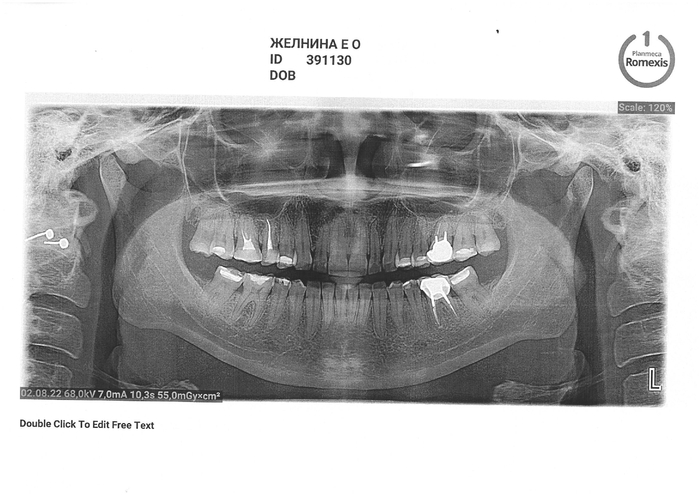

1 декабря: осматривают, обеззараживают, отправляют в дежурный кабинет, где мне говорят: "А какого черта тебя не к нам сначала направили, а сразу в хирургию?". Опять осмотр, рассказ с самого начала о том, что случилось, заполнение карточки, рентген, записали на 7 декабря для установки пломбы.

Дождался, в очередной раз рассказал всю свою историю этой эпопеи, сказали, что заложат лекарство и временную пломбу пока что, 40 минут в кресле пролежал с открытым ртом, благо не больно совсем... Теперь 29 декабря на постоянную пломбу идти...